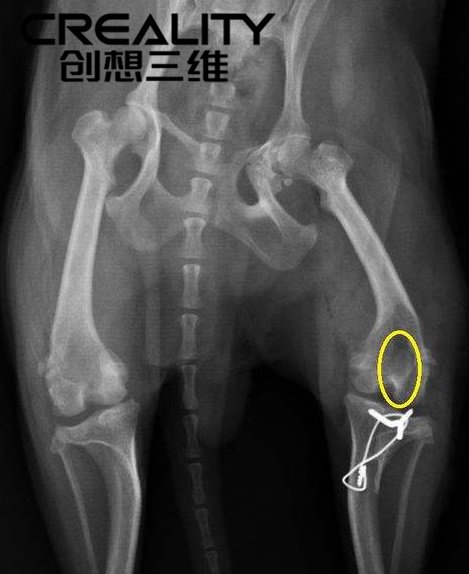

傳統上,這些動物是通過植入的無線電發射器進行追蹤的,但這涉及到手術,而且風險很大。手術本身可能會造成傷害,或者植入物會移動到身體的其他部位。尼爾評論道:“風險相當嚴重,你只有不到四分之一英寸的切口來安裝植入物。有報道說植入物卡在了盆腔管內,要么導致嚴重便秘,要么阻塞產道,要么流血至死。所以必須要有一種辦法來消除對動物的傷害。

但正如尼爾之前提到的,我們需要跟蹤小山貓。用傳統材料制造的項圈會對山貓造成不適,最大的問題是它們的尺寸。小動物長得很快,項圈也需要適應。

尼爾解釋說:“似乎我們使用的所有技術都是最先進的,比如GPS等等。但是,這看起來像是70年代的附著物,我們使用防水織物和不同的螺栓附著物。目前,對于小貓和其他成長中的動物來說,唯一的解決辦法就是植入,但是植入物對于你能聽到的東西來說,范圍很小,就像實際發出的信號一樣。此外,還要考慮傳送器將始終與動物在一起。”

有了3D打印制造,這一挑戰得以解決。尼爾用高速成型樹脂開發了第一個可膨脹領的原型,還用堅固的尼龍6制造了第二階段的原型。

3D打印制造是這個問題的最終解決方案,因為它提供了絕對新的可能性。這不僅給了尼爾設計的自由度和舒適定制衣領的能力,而且加速了原型制作過程,使他能夠測試柔性材料。如果沒有3D打印,這個項目就不會發展得這么快。